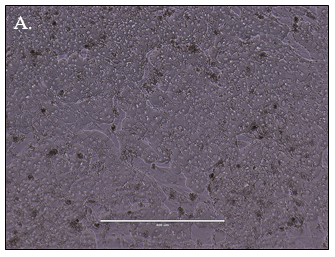

Predicting human hepatic clearance (CLhepatic) is often challenging in early drug development, particularly when low-clearance compounds are involved. To assess the metabolic stability of such drugs, suspended primary human hepatocytes (PHH) are commonly used; however, their ability to accurately predict in vivo CL, particularly of slowly cleared drugs, can be limited by short incubation times and rapid loss of enzymatic activity. To mitigate these issues, long-term in vitro models, like the Triculture System (TCS) developed by LifeNet Health, have been implemented in an effort to improve the characterization of hepatic metabolism and clearance in vitro by lengthening the amount of time hepatocytes can be cultured successfully. The TCS is an all-human cell-based in vitro model comprised of PHH and two different types of primary feeder cells (FC) that are plated together, shown in (Figure 1), on either a 24-well or 96-well collagen-I coated plate. In this study, the TCS (in both 24- and 96-well formats) was assessed for its functionality and its ability to predict human CLhepatic over the course of a 7- day incubation with no media change.